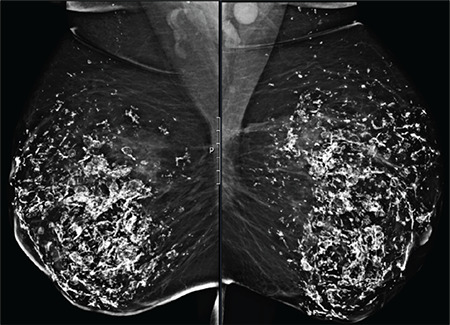

Figure 3.

An MLO view of both breasts shows bilateral diffuse, coarse, and curvilinear calcifications, starting under the skin and scattered across the whole parenchyma of the breasts bilaterally

MLO: Mediolateral oblique

On sonographic examination, axillary lymphadenopathy and ill-defined isoechoic masses, with acoustic shadows related to coarse dystrophic calcifications in the breast parenchyma, were observed. These findings were compatible with fat necrosis (Figures 1 and 2). On the mammogram, diffuse calcifications starting under the skin and scattered bilaterally in the whole of the breast parenchyma were observed. These diffuse calcifications had a coarse and curvilinear shape, consistent with the fat necrosis (Figure 3).

In our case, there were coarse and curvilinear calcifications on the mammogram and isoechoic masses with axillary lymphadenopathy on ultrasound.